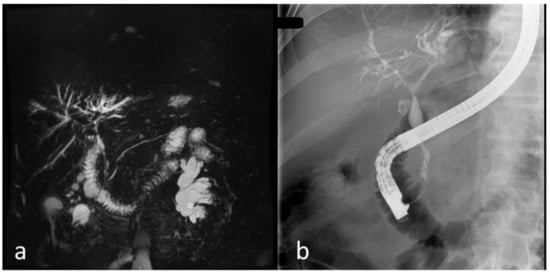

5.4. Imaging